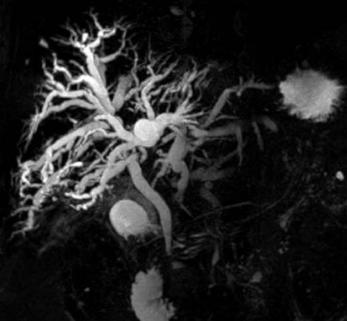

Использование МРТ брюшной полости и холангиографии одновременно применяется при онкологическом поиске. Подход направлен на выявление атипичных узлов диаметром свыше 1 мм (при сканировании на высокопольном оборудовании мощностью от 1,5 Тесла). Построение трехмерной реконструкции на основе томограмм с шагом в один миллиметр получается высококачественным пространственным отображением, позволяющим специалистам тщательно отслеживать ход и направление протоков, состояние окружающих тканей.

Желчь является естественным контрастом, насыщенным атомами водорода, поэтому хорошо визуализируется при магнитно-резонансной томографии. Отменное качество изображения получается даже после трехмерного моделирования, позволяющего врачам рассмотреть орган со всех сторон.

Магнитно-резонансная холангиография выполняется в лежачем положении. Для устранения помех нужна задержка дыхания на 12 секунд. Лучшее качество изображений получается на высокопольных аппаратах. Длительность – 20-30 минут.